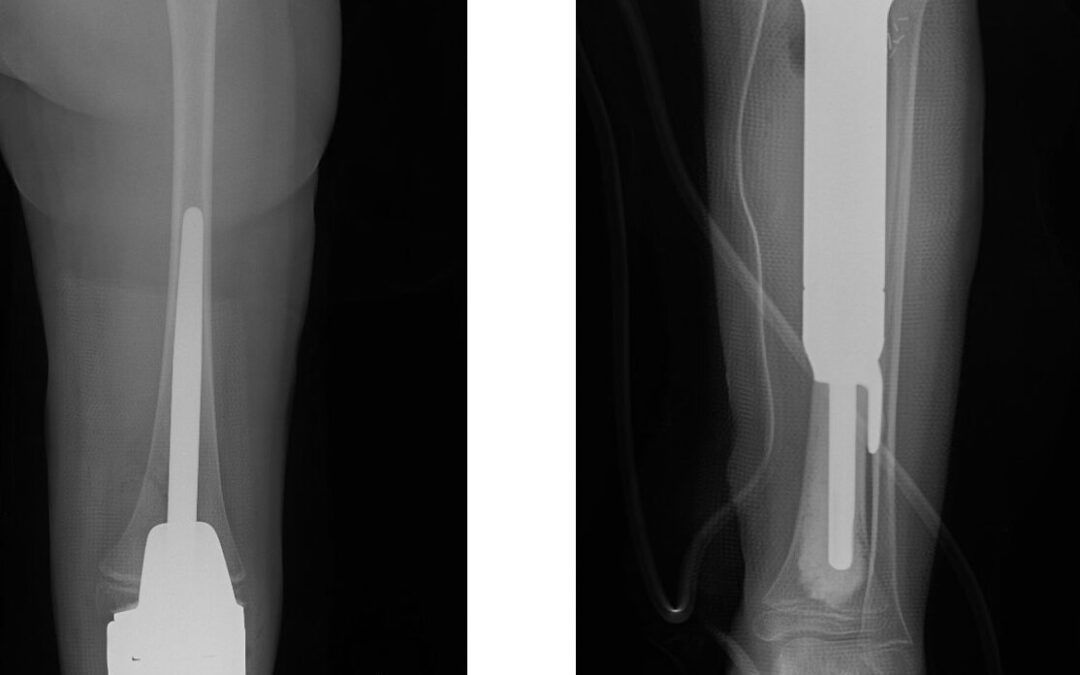

It is a procedure that involves removing a tumor, usually malignant or benign aggressive, of the proximal tibia (upper part of your shin bone near knee joint) and in most instances replacing the bone and knee joint with a special customizable proximal tibia tumor prosthesis.

It is a procedure that involves removing a tumor (usually malignant or benign aggressive) of the lower part of the thigh bone (femur) and in most instances replacing the bone and knee joint with a special customizable distal femur tumor prosthesis.